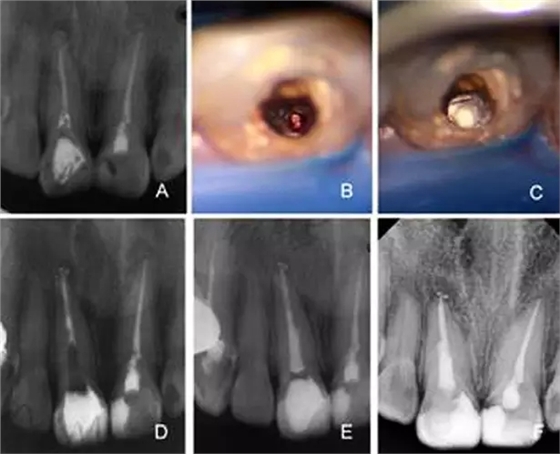

1.webp.jpg

2.webp.jpg